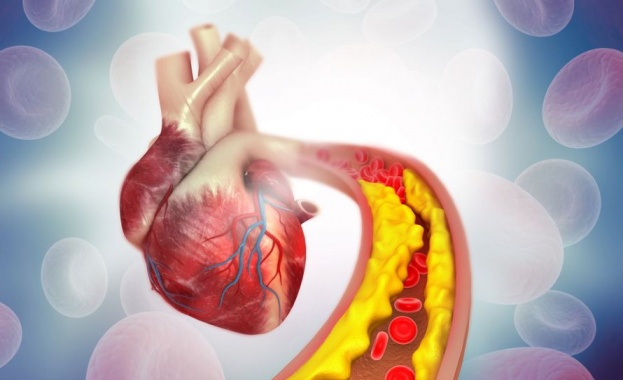

Ето това масло помага в борбата срещу високия холестерол

Д-р Кевин Хъфман, бариатричен лекар и главен изпълнителен директор на Ambari Nutrition, вярва, че маслото от авокадо може да има решаващо значение за здравословното състояние на вашата празнична трапеза. Това се дължи най-вече на „мононенаситените мазнини", които могат да помогнат за намаляване на „лошия холестерол" в кръвта.

„Тези масла са мононенаситени мазнини, което означава, че съдържат много повече хранителни вещества и могат да подобрят нивата на холестерола", казва той пред пациент и добави: „Превръщането на картофеното пюре в пюре от карфиол също предлага креативна и питателна замяна на гарнитури."

Д-р Хъфман със сигурност не е единствен в своите възгледи, тъй като различни други експерти също са възхвалявали ползите от маслото от авокадо. Сред тях са двама учени от китайския земеделски университет Хунан, които миналия месец изложиха изненадващите му ползи в научен обзор.

Сред многобройните компоненти, на които те обръщат внимание, са мастните киселини и богатото количество „фитостероли", като последните се свързват с потенциално по-ниски нива на холестерола. Въпреки това са необходими допълнителни изследвания, за да се разберат по-добре тези връзки.

„Маслото от авокадо има защитен ефект срещу хиперлипидемията, като понижава нивата на TC, TG и LDL-C и защитава липопротеиновия холестерол с висока плътност - поведение, което може да се дължи на високите нива на MUFA, фитостероли и токофероли", пишат експертите от проучването.

„Изключителният потенциал на маслото от авокадо като здравословна храна има много предимства, сред които присъщите хранителни вещества на мастните киселини, фитостеролите, ПХ, токоферолите и мастноразтворимите пигменти са изследвани по-обстойно. Все още обаче са недостатъчни проучванията за това дали други мастноразтворими витамини (като витамин К), съдържащи се в авокадото, влизат в маслото от авокадо по време на процеса на екстракция, както и за тяхното съдържание, стабилност и биологична активност", добавиха те.